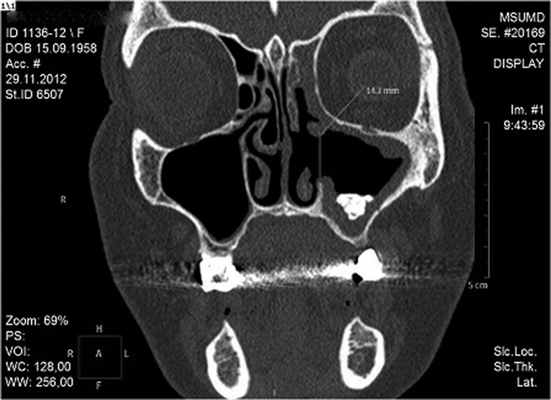

На основании жалоб пациентки на чувство заложенности левой половины носа, дискомфорт в лобной и подглазничной областях слева, внешнего осмотра (незначительный отек щечной области слева, слабо болезненная пальпация подглазничной и щечной областей слева), а также дополнительных методов исследования (ОПТГ, МСКТ-исследование) поставлен диагноз: хронический одонтогенный верхнечелюстной синусит слева. Инородное тело в верхнечелюстной пазухе слева. Состояние после ранее проведенной эндоскопической левосторонней гайморотомии. Больной было проведено оперативное вмешательство в объеме повторной гайморотомии по Колдуэллу-Люку с забором содержимого пазухи. Во время операции из пазухи были удалены полипозно измененная слизистая оболочка, мелкие частицы пломбировочного материала, а также основной фрагмент размером 2×4 мм (рис. 2). Рисунок 2. Та же больная. МСК-томограмма в коронарной проекции до операции. Объем левой ВЧП уменьшен за счет воспалительной гипертрофии слизистой оболочки, стенки пазухи утолщены, склерозированы. Присутствует послеоперационный дефект верхних отделов медиальной стенки в левой ВЧП. Определяется скопление пломбировочного материала. Проведено гистологическое исследование, по данным которого обнаружены мелкие полиповидные кусочки слизистой, выстланные местами эпителием типа респираторного, местами - плоским, местами эпителий слущен, в подлежащих слоях - фиброзная ткань с хронической выраженной воспалительной инфильтрацией, с преобладанием лимфоцитов. Морфологическая картина хронического полипозного синусита.